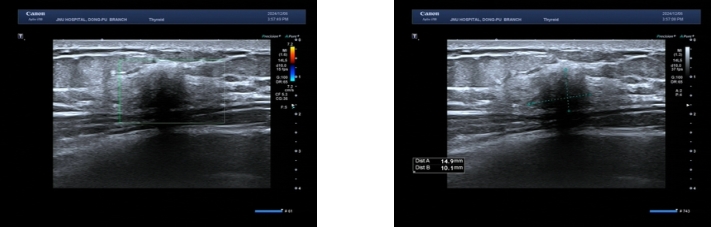

图1 患者入院乳腺彩超图(右乳见一低回声光团,边界欠清,形态欠规则,内部回声均匀,后方无声影;彩色多普勒血流显像未见血流信号)Fig.1